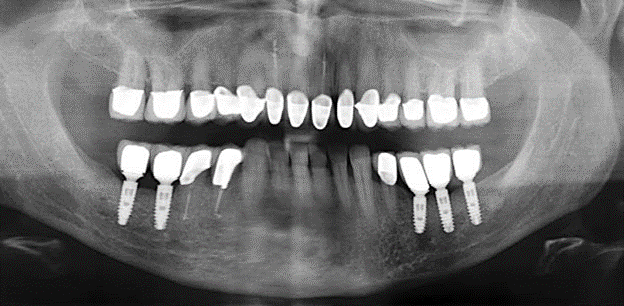

Un paziente di 52 anni si è presentato nella nostra clinica per la prima volta nel 2004 a seguito della perdita dei denti nel terzo quadrante, esprimendo il desiderio di un nuovo restauro protesico. La diagnostica parodontale e radiologica ha rivelato la necessità di un ampio trattamento parodontologico. Inoltre, ai denti 48, 28 e 27 è stata attribuita una prognosi molto scarsa e sono stati successivamente estratti (Fig. 1). A seguito del trattamento periodontologico sistematico completato con successo, è stato inserito una protesi dentale fissa con l'inserimento di cinque impianti nelle regioni dentali 35, 36, 37, 46 e 47. Il trattamento protesico dei denti naturali è stato effettuato con corone rivestite in ceramica di biossido di zirconio; gli impianti two-piece composti da abutment singoli in biossido di zirconio e corone similmente rivestite in ceramica di biossido di zirconio (base Cercon colorata, Dentsply Sirona Lab). L'inserimento definitivo del restauro protesico è avvenuto nel 2005.

Il controllo decennale non ha rivelato alcuna indicazione dell'avanzamento della perdita di attaccamento clinico o della perdita di sostanza ossea perimplantare (Fig. 3).